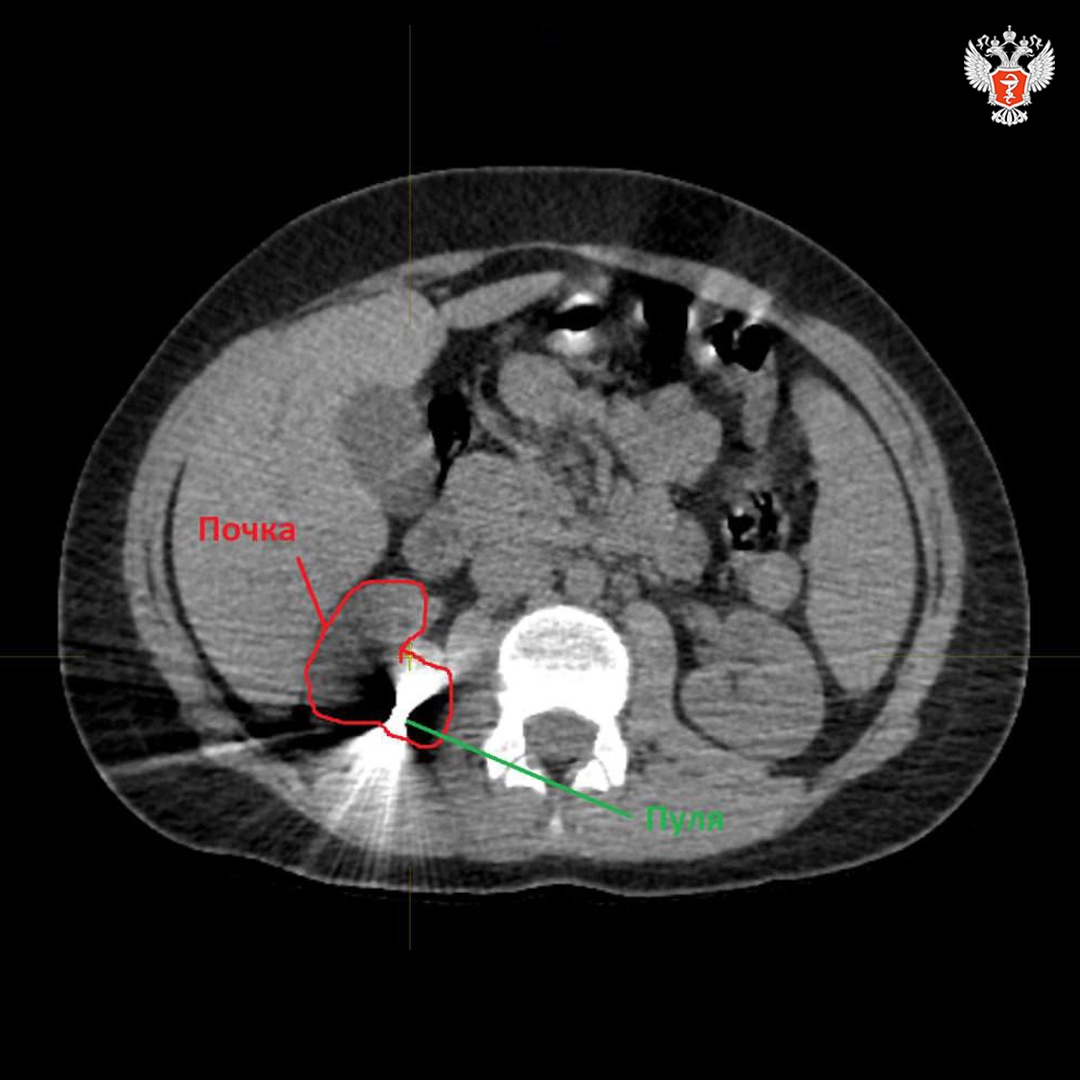

В Новгородской областной детской клинической больнице успешно провели операцию по извлечению пули из почки подростка, получившего ранение из пневматической винтовки.

👨⚕️ После поступления в больницу врачи провели комплексное обследование пациента. Было установлено, что пуля прошла через мягкие ткани и застряла в почке. После стабилизации состояния ребенка хирурги приняли решение о проведении операции.